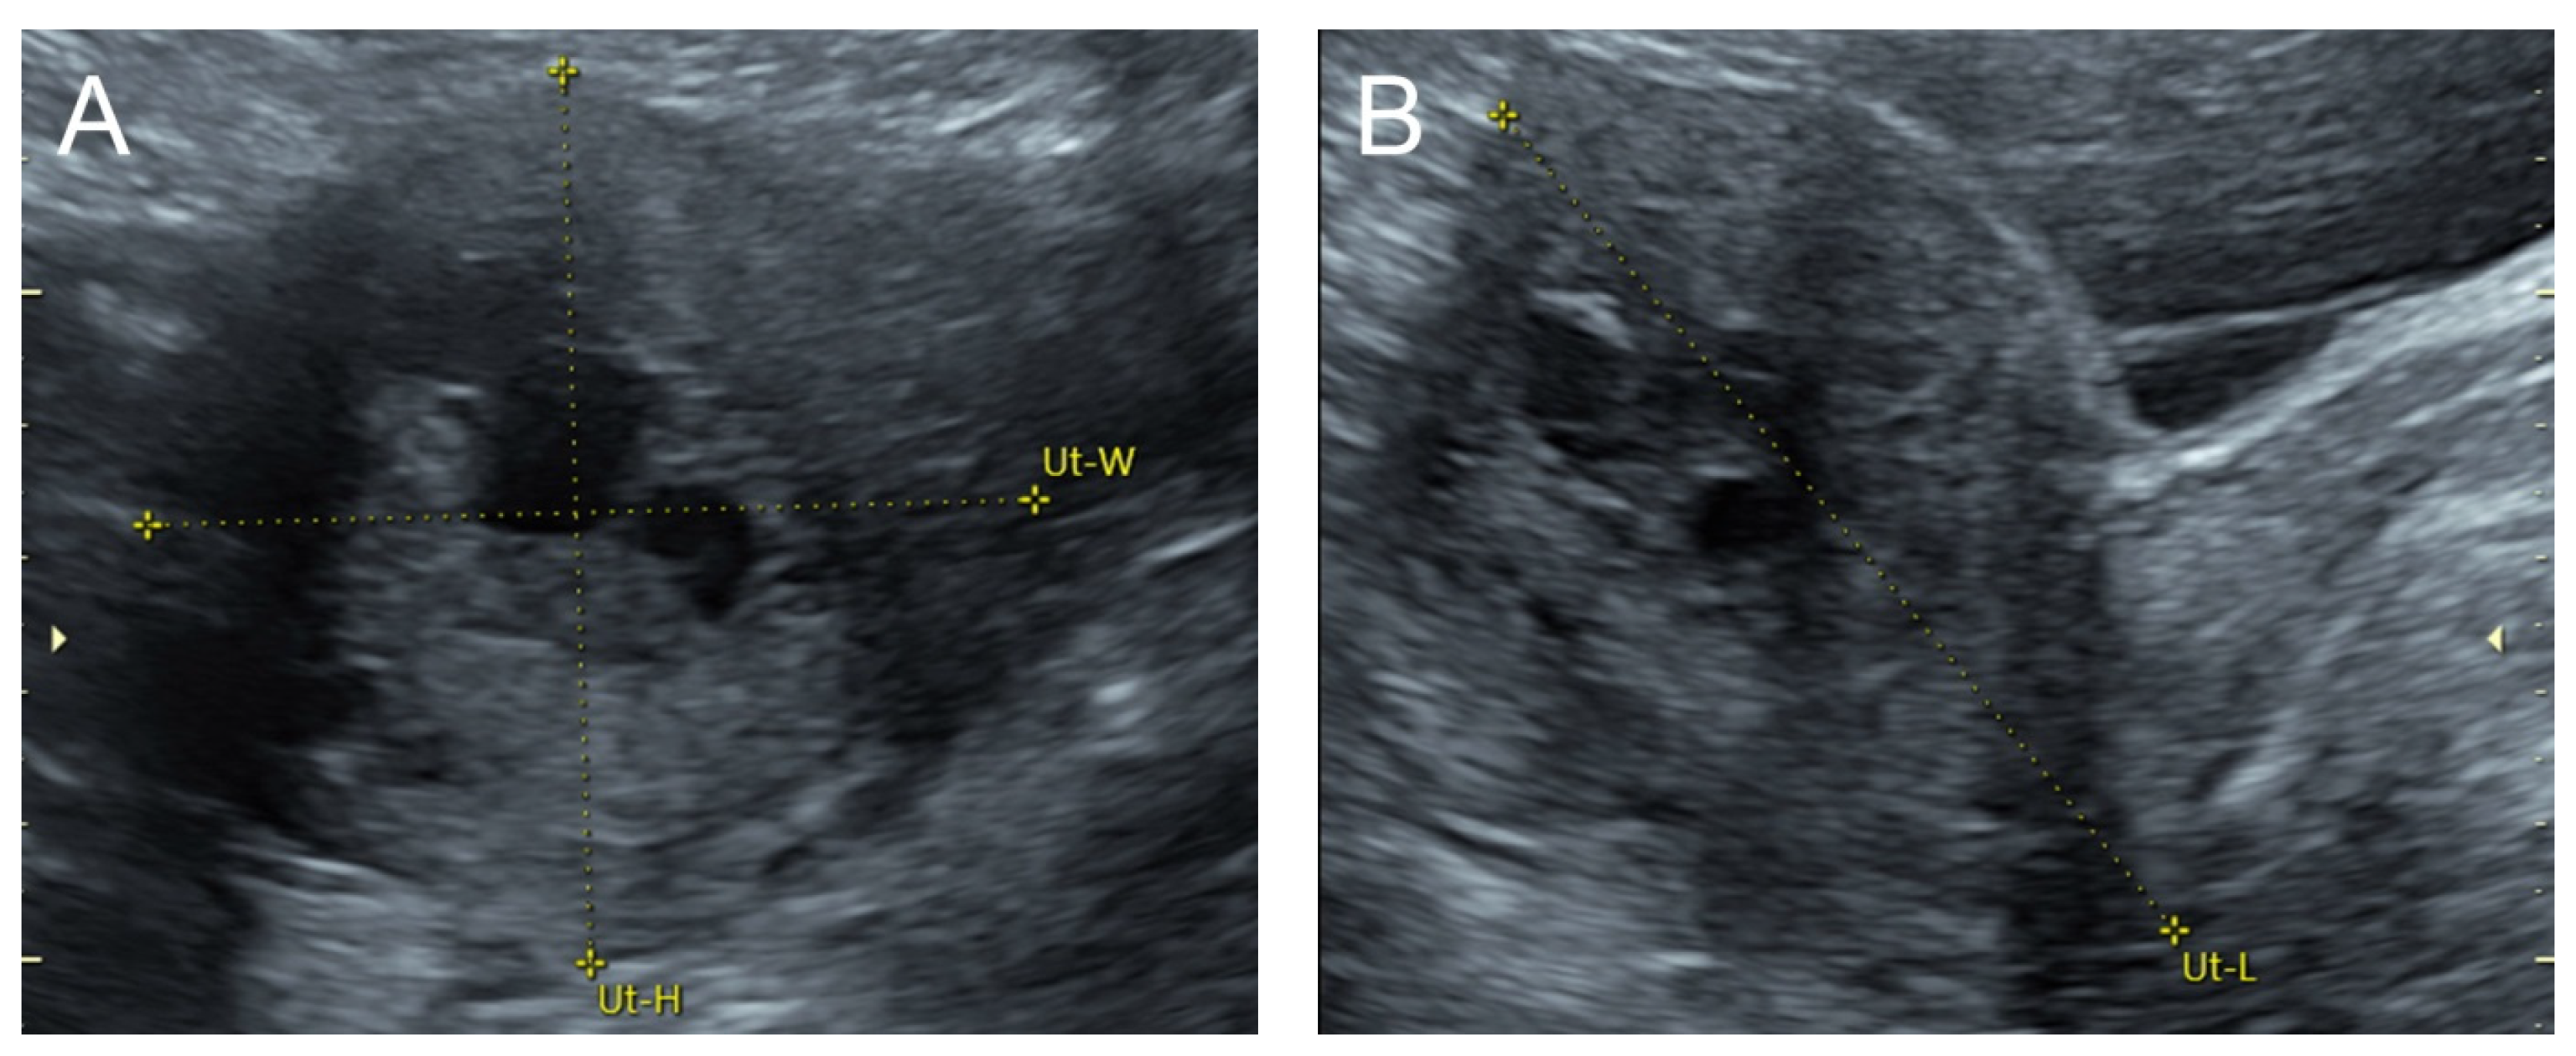

2. Case 1 (Figure 1)

A 32-year-old woman, P1011, presented with abnormal vaginal bleeding 4 h prior to admission, with no other symptoms. Her last pregnancy, 3 years prior to this admission, was a term pregnancy complicated by postpartum hemorrhage due to a retained piece of the placenta, and manual removal of the placenta was performed. Her underlying disease was controlled hyperthyroidism (euthyroid state, normal thyroid function test). The general physical examination was normal. Pelvic examination revealed no structural abnormalities, except active bleeding per the cervical os. The basic laboratory work-up and hematologic study showed a normal hemoglobin level of 12.1 g/dL. Her serum beta-hCG was less than 0.2 mIU/mL. Two-dimensional ultrasound and color Doppler examination indicated uterine AVM. Abdominal CTA indicated uterine AVM.